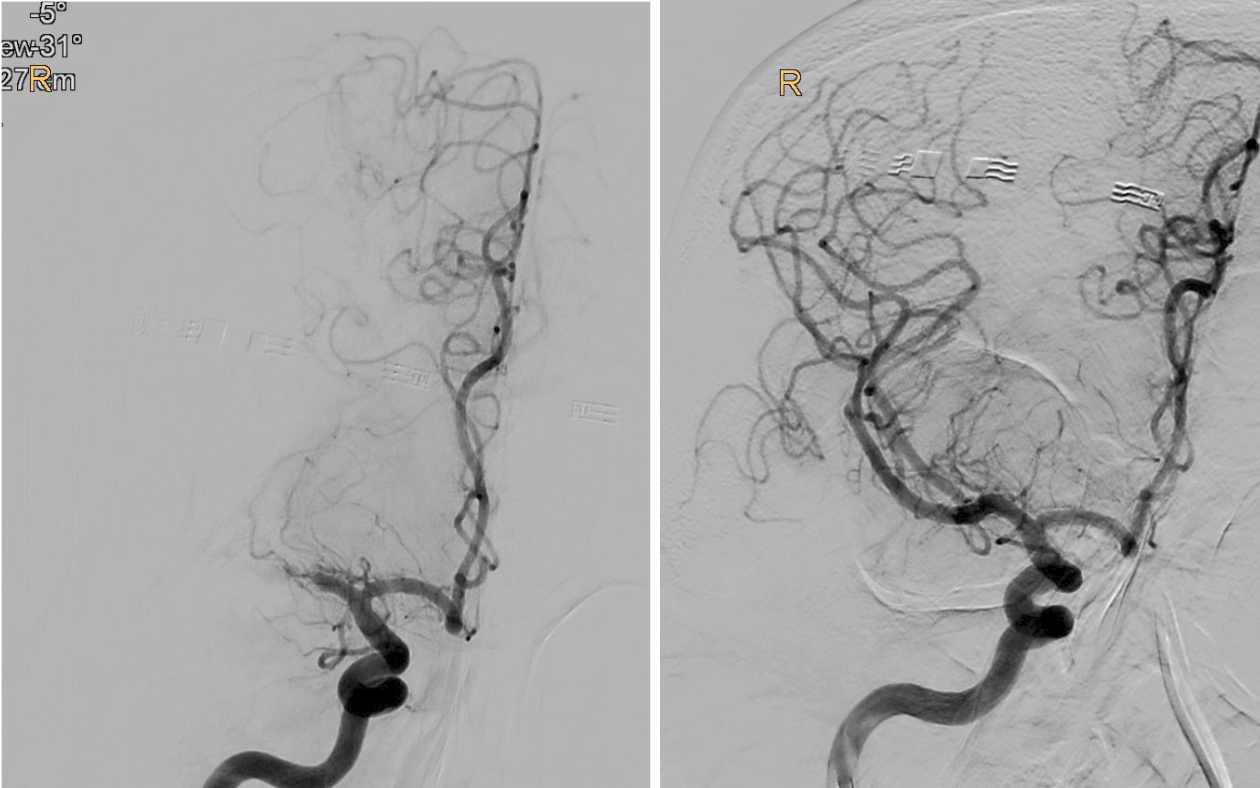

BU: Verschluss des mittleren Hirngefäßes in der Angiographie dargestellt (l.), und wieder eröffnet (r.). Bilder: Univ.-Klinik für Radiologie

„Bei der Thrombektomie bringen wir mit einem Spezialkatheter von der Leiste ausgehend einen Stent an der Stelle des Gehirns ein, wo das Gerinnsel sitzt. Mit einer Saugvorrichtung wird das Blutgerinnsel dann zusammen mit dem Stent herausgezogen. Das Ganze passiert unter Röntgenkontrolle und bedarf viel Erfahrung“, erklärt Gizewski den sensiblen Vorgang.

„Bei einem Schlaganfall zählen einerseits Zeit und andererseits die noch verbliebene Sauerstoffversorgung des Gehirns, welche bei den Patient:innen unterschiedlich ausfällt. So genannte Kollaterale, Gefäß-Querverbindungen, können die Durchblutung noch einige Zeit aufrechterhalten. Je weniger solcher Kollateralen vorhanden sind, desto weniger Zeit hat man. Doch auch wenn schon Gewebe untergegangen ist, kann man noch etwas retten, wenn man thrombektomiert. Das konnten wir jetzt mit der TENSION-Studie zeigen“, berichtet Gizewski. Viele der Patient:innen könnten trotz der bedrohlichen Ausgangssituation jetzt wieder ein eigenständiges Leben führen. Nachdem sich der Erfolg der Katheter-Behandlung (insgesamt 125 Patient:innen) in der randomisierten Studie im Vergleich zur besten konservativen medizinischen Behandlung (128 Patient:innen) schnell gezeigt hatte, wurde die Studie frühzeitig beendet.